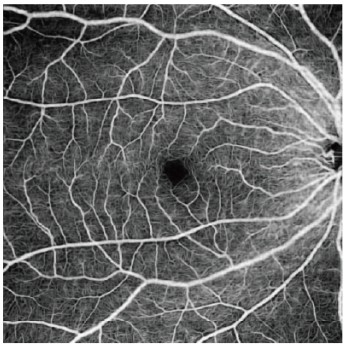

三次元画像解析装置 Triton Plus Pro(Topcon)

三次元画像解析装置(OCT)は現代の眼科に必要不可欠な機器の一つで、主に網膜の層構造を詳細に可視化することで、多くの網膜病変の発見や評価、また治療効果の判定などが的確に行えるようになりました。また視神経乳頭周囲の神経線維の厚さを解析することで緑内障の評価が可能となったり、Angiographyといって網膜血管や脈絡膜血管の血流を造影剤を用いることなく評価することができ、低侵襲で眼底の状態を把握することができるようになりました。 Triton Plus ProはTopcon社が提供する最新鋭のOCTで、眼科臨床で必要とされるすべての機能を高いレベルで可視化することができ、従来機器では評価が難しかった硝子体や網膜、脈絡膜までも鮮明に描写されるようになりました。